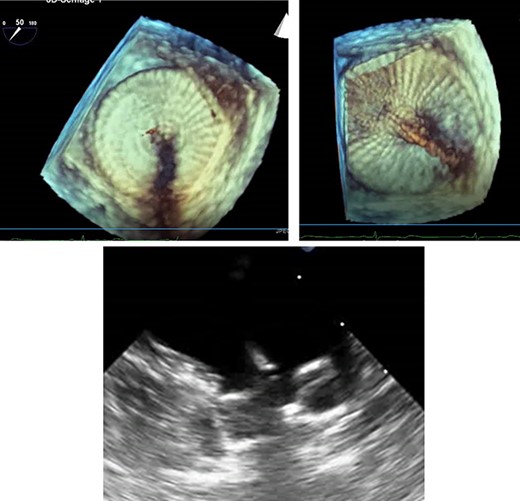

A treatment review for AF was undertaken, but no further action such as MAZE, pulmonary vein isolation, electrophysiology intervention or rhythm control were considered viable strategies. An LAA occluder implantation (Amplatzer Amulet LAA Occluder, Abbott) was carried out under transoesophageal echocardiography (TEE)-guidance and general anaesthesia (Figs 1 and 2). The left atrium was accessed via the right femoral vein (7F 8.5F catheter). The transseptal puncture with an SL1 catheter was pressure-controlled and TEE-guided posterior–inferior, straight to the optimal position. A 6F pigtail catheter was inserted for LAA angiography in right anterior oblique 30°, cranial 20° and caudal 0°.

Cardiac catheterization: LAA occluder implantation; interventional LAA occluder implantation via the right femoral vein and septal puncture under radioscopy and transoesophageal echocardiography (TEE) control.

TEE for interventional LAA occluder implantation; TEE controlled, unsuccessful LAA occluder implantation due to difficult LAA morphology.

The patient’s anatomy showed a large funnel-shaped ostium, with narrow neck and shallow depth and chicken-wing morphology with 90° anterior/frontal angulation. TEE measurements showed a landing zone diameter of ~12–13 mm. A 16 mm occluder was selected. The TorqueVue lock 12F was exchanged via a stiff wire and positioned in the left superior pulmonary vein. No satisfactory position was achieved. For the proximal part, shortly after the ostium with a maximum depth of 12 mm the occluder was too small and exchanged for a 20 mm occluder. This could not be securely positioned; the corpus dislocated in the Timed Up and Go test because of limited contact with the LAA surface. A new transseptal puncture was performed in a more posterior and superior position, the CS catheter removed, and the 7F sheath changed to the SL1. The Amplatzer Amulet 16/20/25 mm LAA occluder implantation remained challenging due to the unusual anatomy with an atypical position of the auricular appendage. Finally the procedure was aborted in favour of a LAA clip.